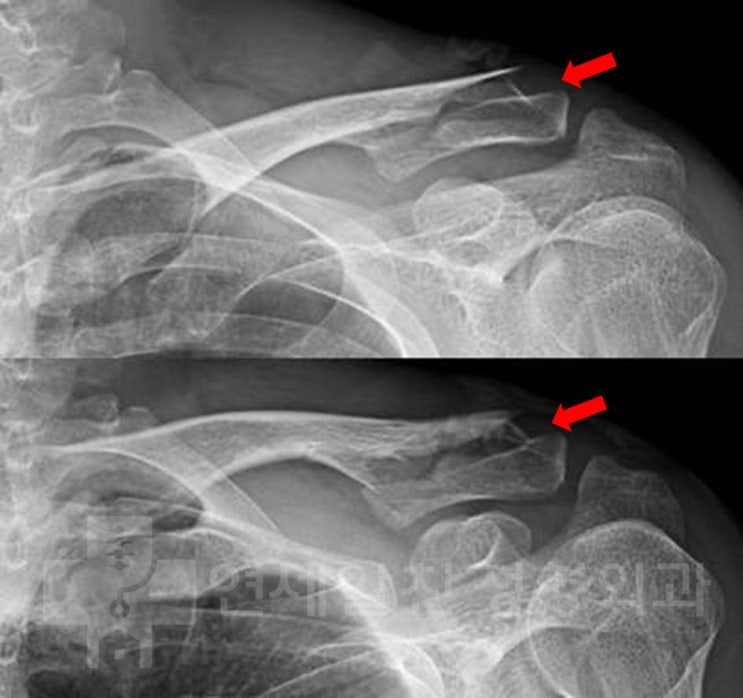

쇄골 원위부 골절에서 해부학적 금속판을 이용한 골절 수술

33세 남자환자로 스키 타다 넘어진 후 발생한 어깨 통증을 주소로 내원하였다. 골절 의심하에 X-ray 검사...